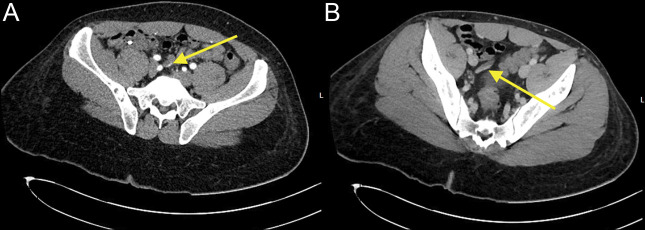

We present a case of hematochezia because of a small arterial bleed endoscopically seen at the appendiceal orifice. The bleed was slowed with hemostatic clip placement, which allowed for preoperative imaging and appropriate resuscitation. The patient was taken for definitive laparoscopic appendectomy with complete resolution of gastrointestinal bleeding.